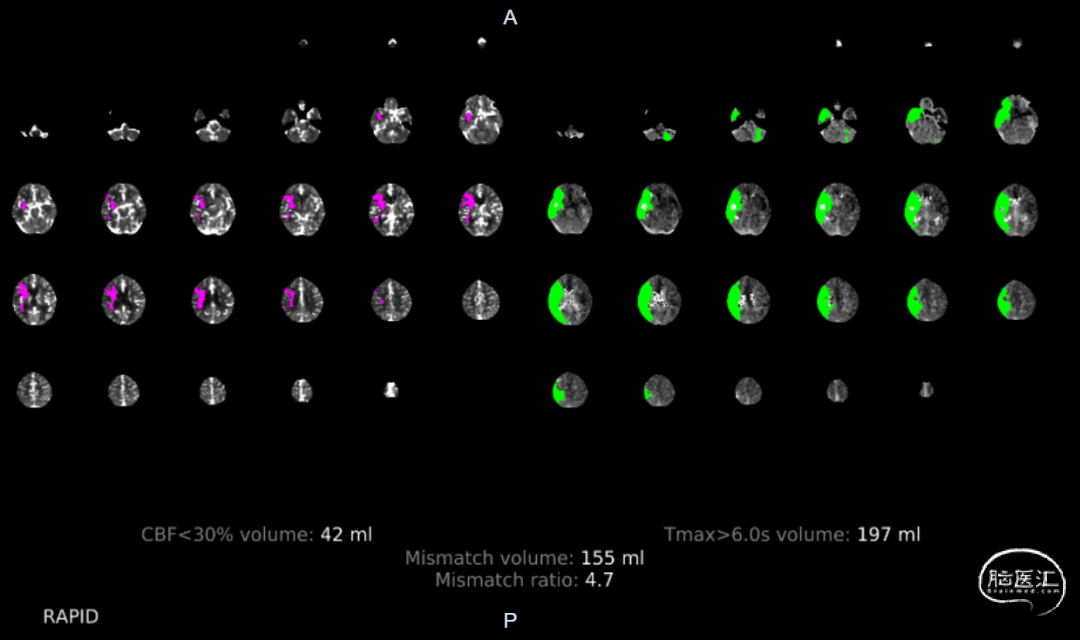

术前影像学检查

脑CT灌注:右侧额叶、颞叶、顶叶缺血低灌注;mismatch 155ml。